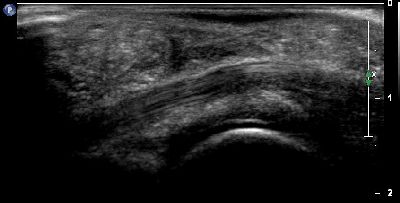

Fascite (img. 01) fascite 01